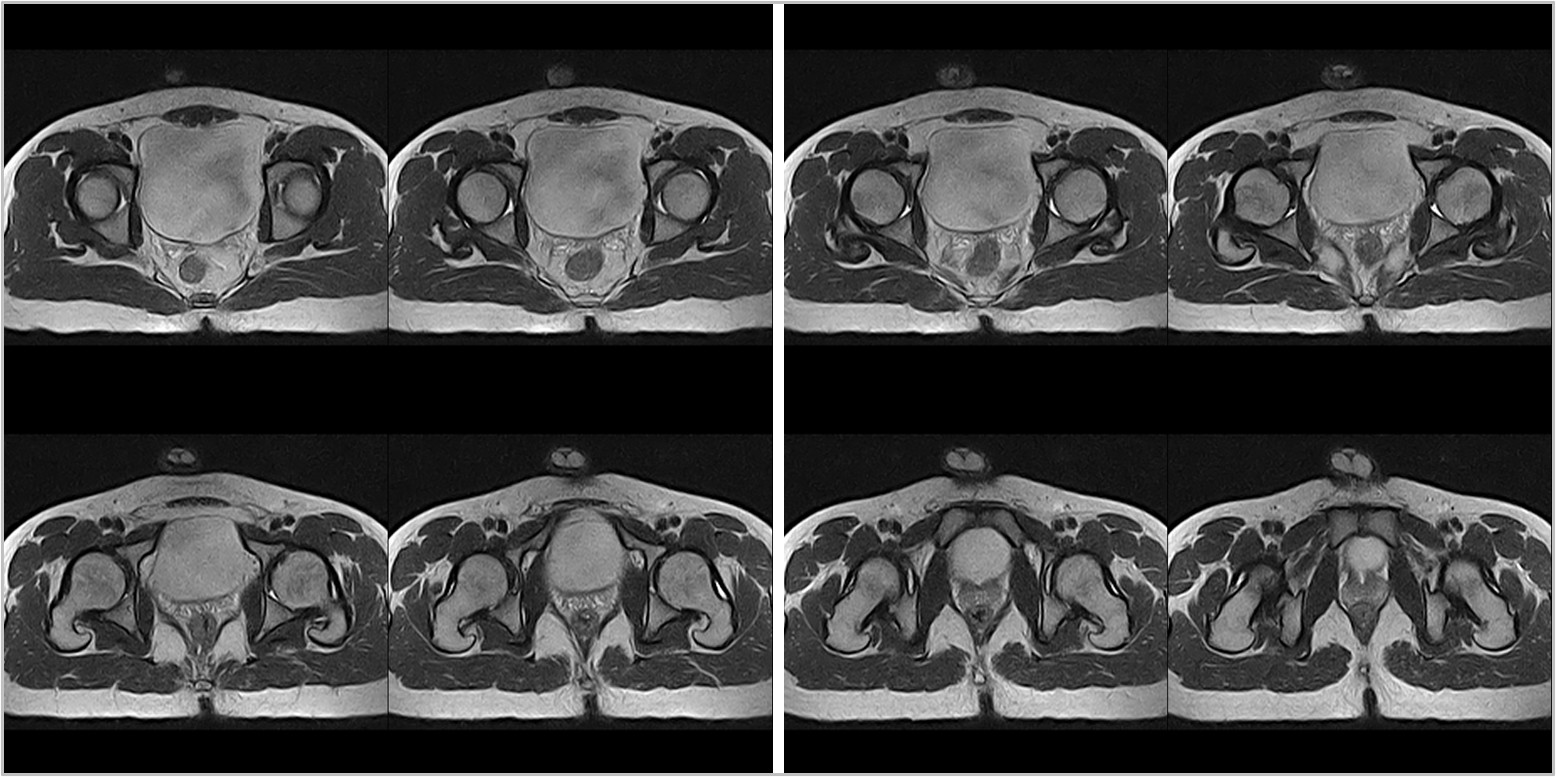

Hình ảnh lâm sàng